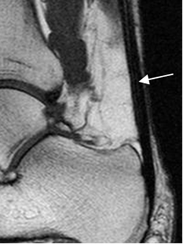

Fig 17. Ligamento calcaneoescafoideo.

A: RM axial en T1 y B: RM sagital en T2. Ligamento hipointenso normal, entre el escafoides y el calcáneo.